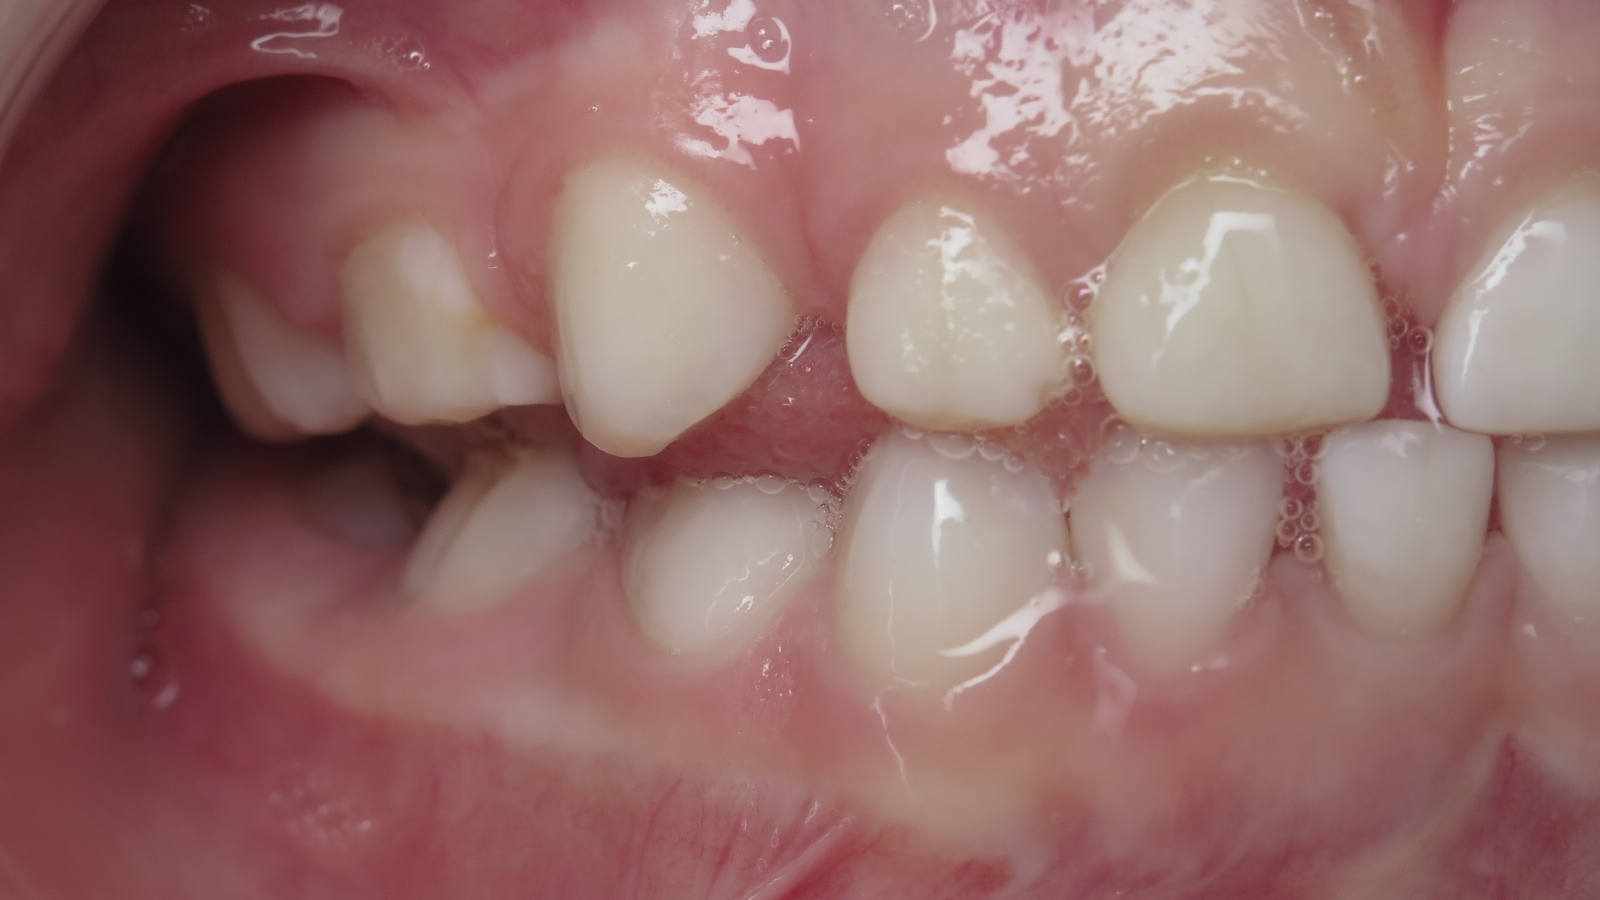

7.inversé droit 4 ans

inversion des dents postérieur coté droit